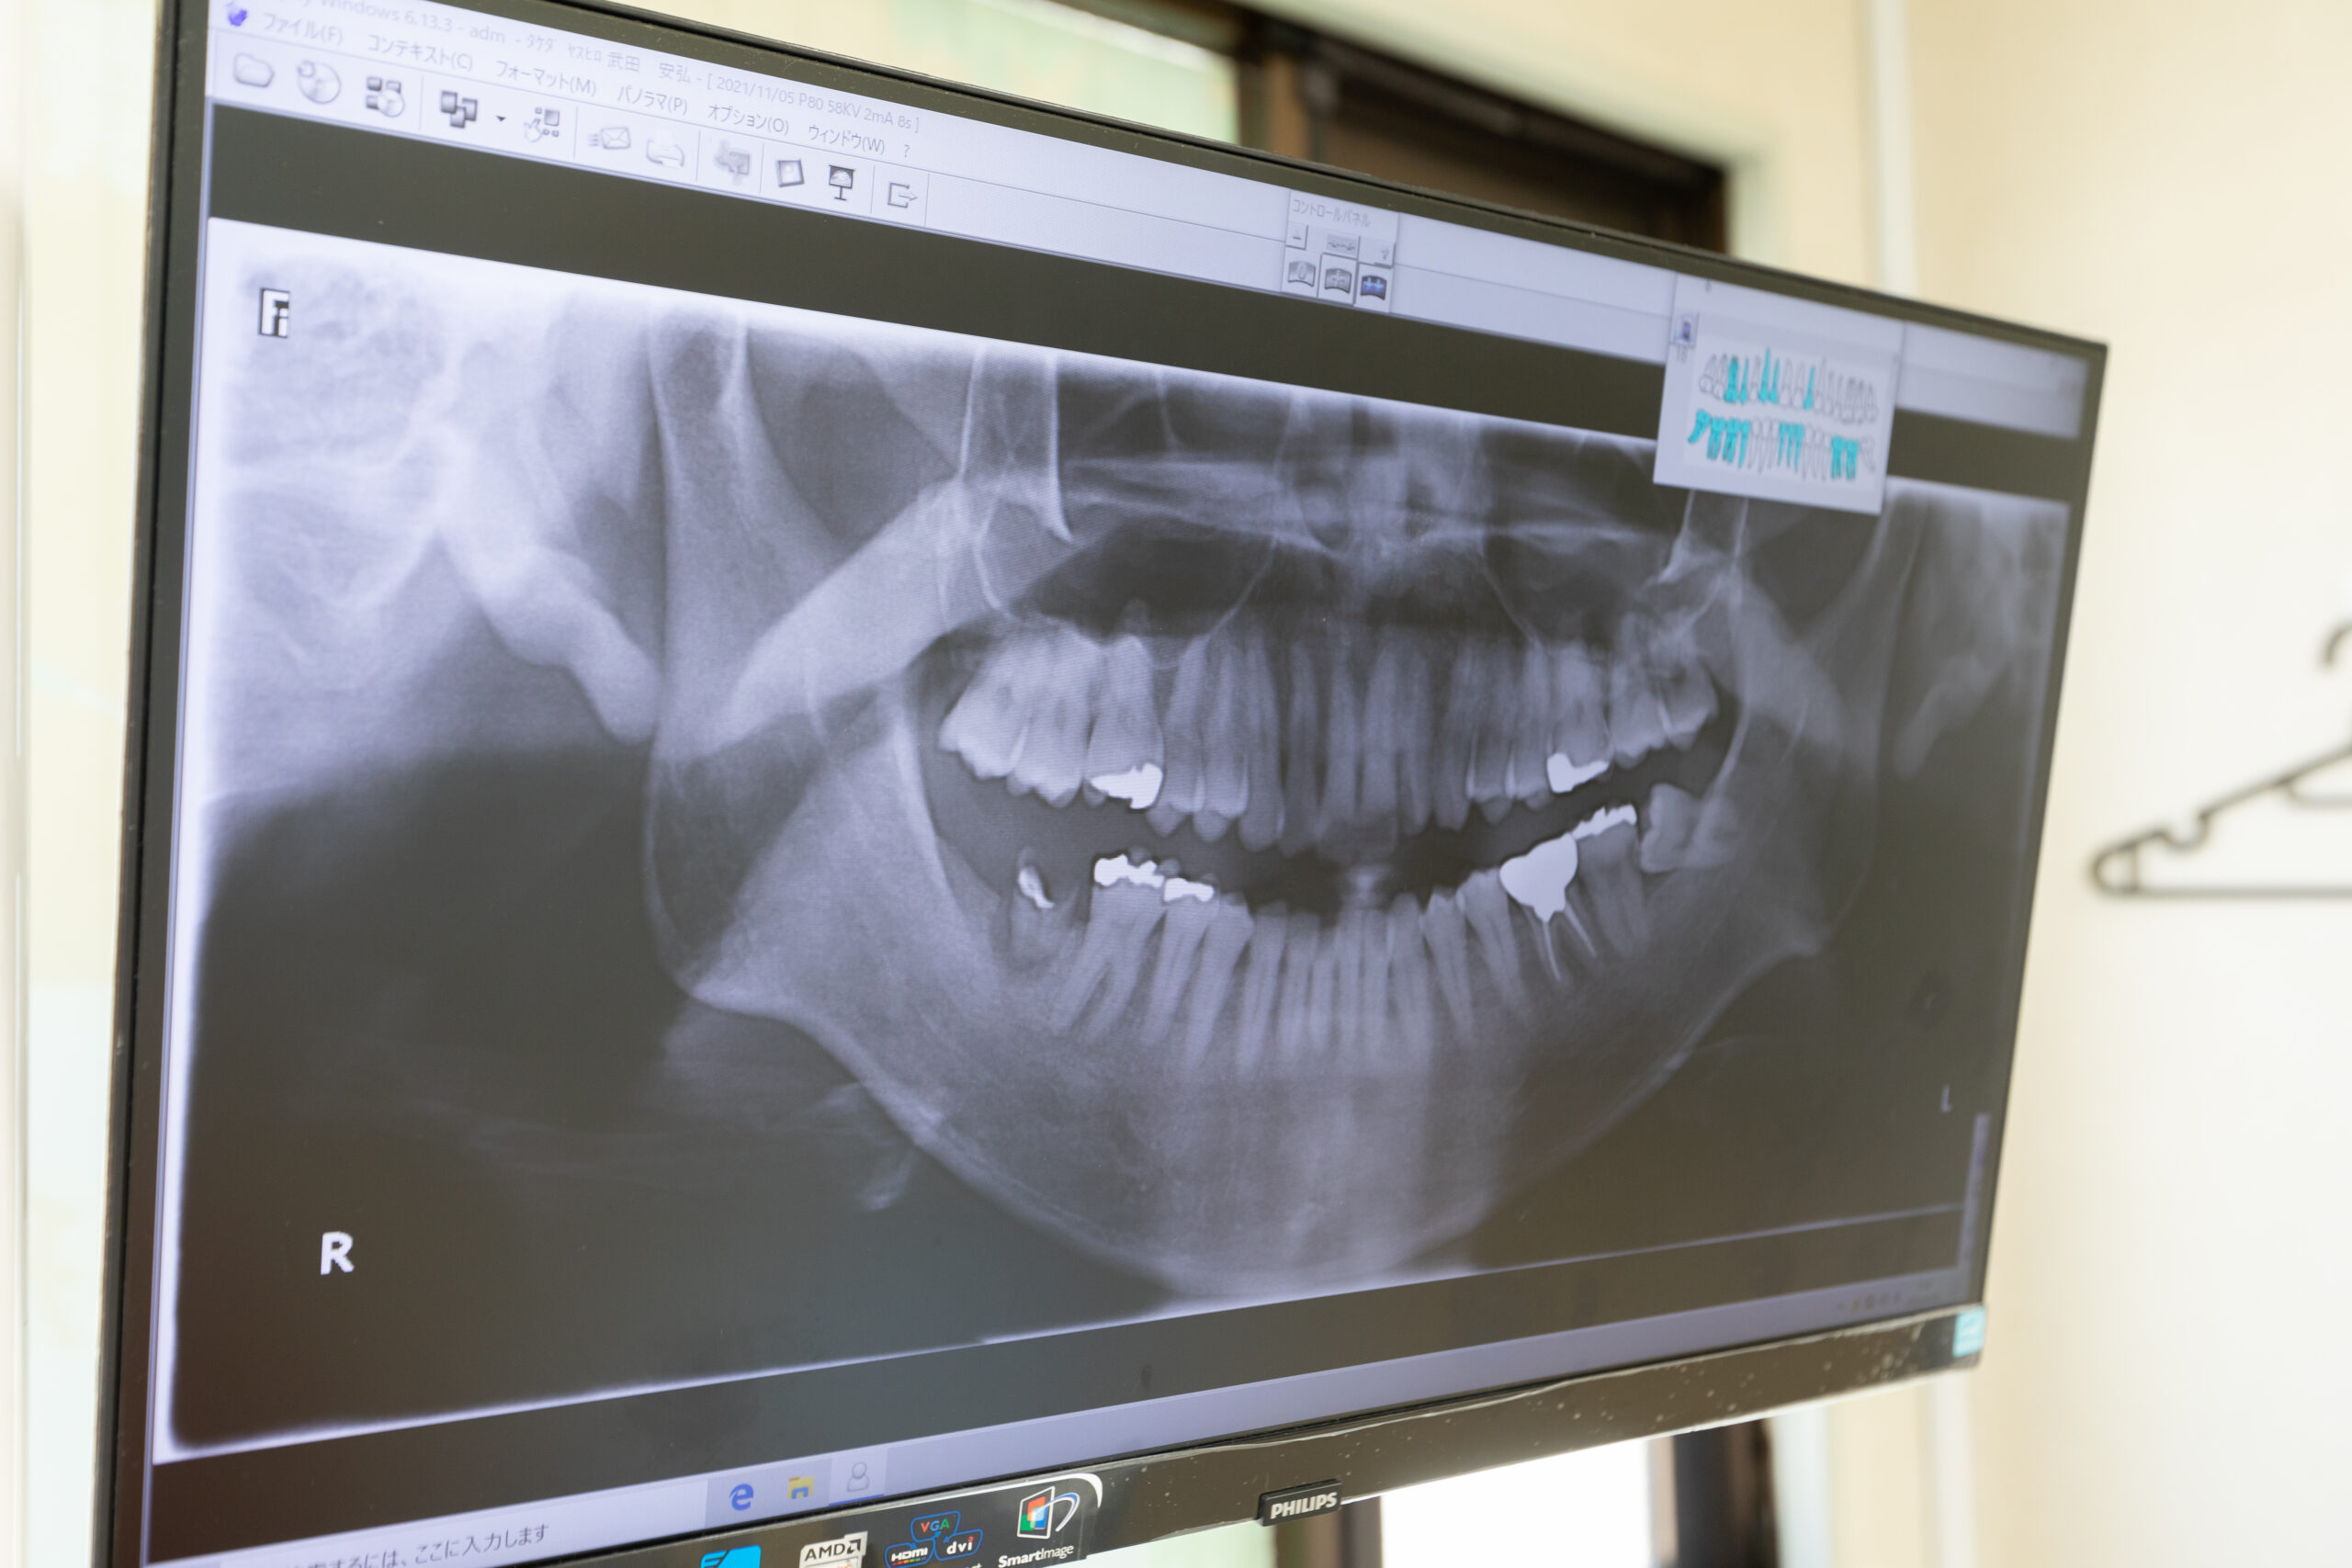

デジタルレントゲンシステム

従来のフィルム式と比較して放射線量を大幅に削減したデジタル方式のレントゲン撮影装置を使用しております。